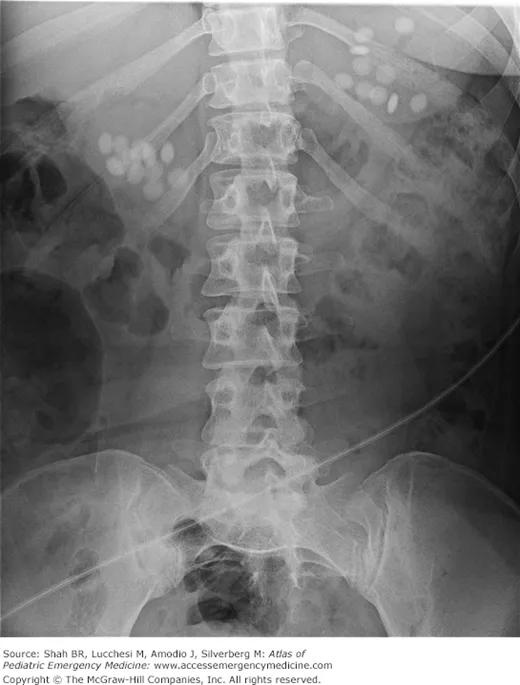

- Diagnosis: Blood Lead Level (BLL), X-ray (lead lines in long bones of children; radiopaque paint chips in GIT), ↑Erythrocyte protoporphyrin (EP).

- Dx: Serum Fe (peak 4-6h), AXR (radiopaque).